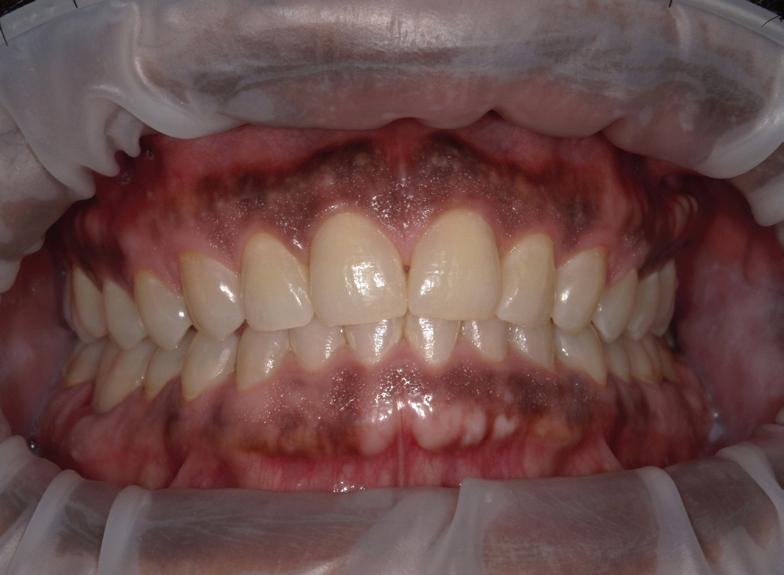

BEFORE AND AFTER PHOTOS

Empowering Dental Health with TeethXpress

TeethXpress implants have revolutionized dental care by offering a comprehensive solution for individuals struggling with missing or failing teeth. Let’s delve into the educational aspects of TeethXpress implants, focusing on their benefits and what to expect from this innovative procedure.

Immediate Results and Lasting Impact

One of the primary advantages of TeethXpress implants is the immediate results they offer. Unlike traditional dental implant procedures that may require multiple visits over an extended period, TeethXpress can often provide a complete set of new teeth in just a few hours. This quick turnaround time allows patients to swiftly regain their ability to eat, speak, and smile confidently.

Improved Dietary Habits and Quality of Life

Preservation of Jawbone and Long-Term Oral Health